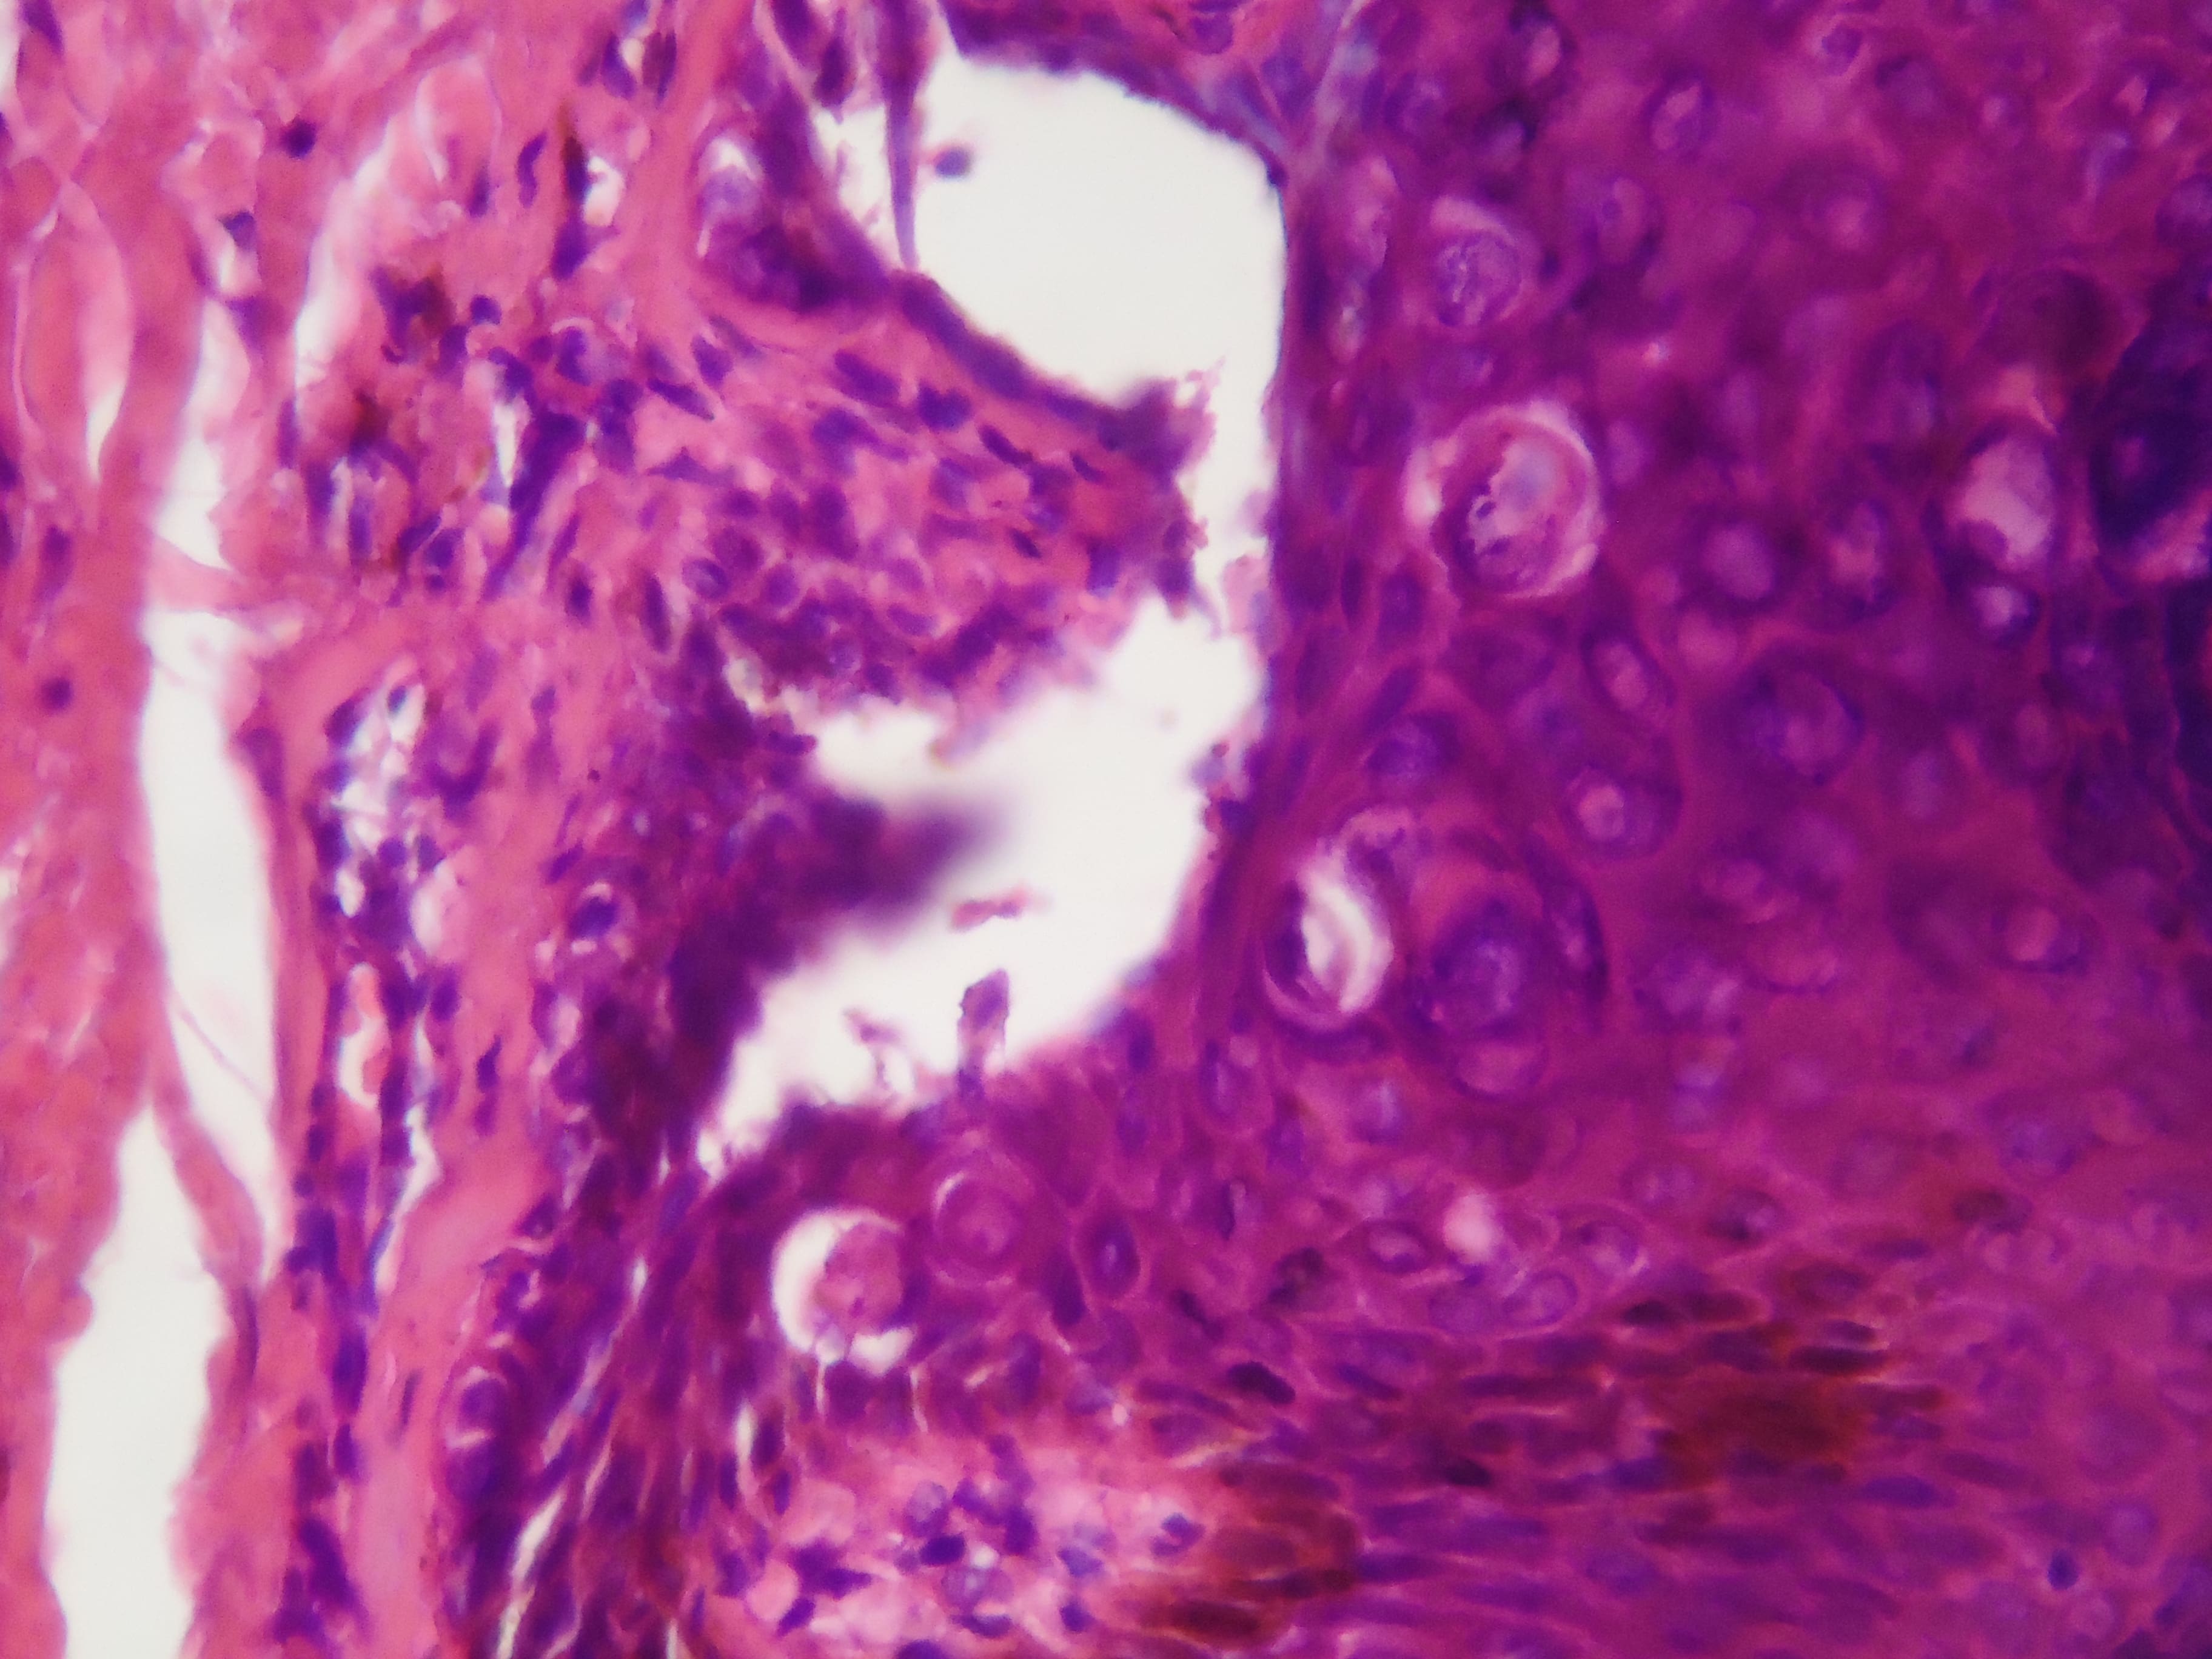

ENFEREMEDAD DE DARIER - HISTOPATOLOGIA